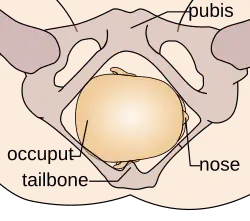

The vertex is the area of the vault bounded anteriorly by the anterior fontanelle and the coronal suture, posteriorly by the posterior fontanelle and the lambdoid suture and laterally by 2 lines passing through the parietal eminences.

In the vertex presentation, the occiput typically is anterior and thus in an optimal position to negotiate the pelvic curve by extending the head. In an occiput posterior position, labor becomes prolonged, and more operative interventions are deemed necessary.[4] The prevalence of the persistent occiput posterior is given as 4.7%.[4]

The vertex presentations are further classified according to the position of the occiput, both right, left, or transverse and anterior or posterior:

- Left Occipito-Anterior (LOA), Left Occipito-Posterior (LOP), Left Occipito-Transverse (LOT)

- Right Occipito-Anterior (ROA), Right Occipito-Posterior (ROP), Right Occipito-Transverse (ROT)

The occipito-anterior position is ideal for birth; it means that the baby is lined up so as to fit through the pelvis as easily as possible. The baby is head down, facing the spine, with their back anterior. In this position, the baby's chin is tucked onto their chest, so that the smallest part of their head will be applied to the cervix first. The position is usually "Left Occiput Anterior", or LOA. Occasionally, the baby may be "Right Occiput Anterior", or ROA.[5]